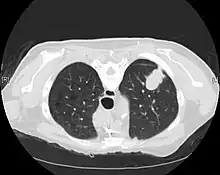

Imaging

CT imaging provides better evaluation of the lungs, with higher sensitivity and specificity for lung cancer compared to chest radiograph (although still significant false positive rate[27]). Computed tomography (CT) that is specifically aimed at evaluating lung cancer includes the chest and the upper abdomen. This allows for evaluation of other relevant anatomic structures such as nearby lymph nodes, adrenal glands, liver, and bones which may show evidence of metastatic spread of disease.[4] Indeed, the US Preventative Services Task Force recommends annual screening with low-dose CT in adults aged 55 to 80 years who have a 30 pack-year smoking history and currently smoke or have quit within the past 15 years, with certain caveats (see Lung cancer screening).[28]

Nuclear medicine imaging, such as PET/CT and bone scan, may also be helpful to diagnose and detect metastatic disease elsewhere in the body.[7] PET/CT uses a metabolically active tracer that allows clinicians to identify areas of the body that are hypermetabolic. Increased uptake of the tracer occurs in malignant cells and areas of inflammation or infection. Integrating the imaging reflective of metabolic activity with normal CT imaging allows for higher sensitivity and specificity compared to PET alone.[4]

MRI is reserved for patients with advanced disease where intracranial, or brain, involvement is likely. It is also helpful for evaluating the extent of chest wall, diaphragmatic, brachial plexus (such as in the case of superior sulcus tumors), or spine involvement.[4]